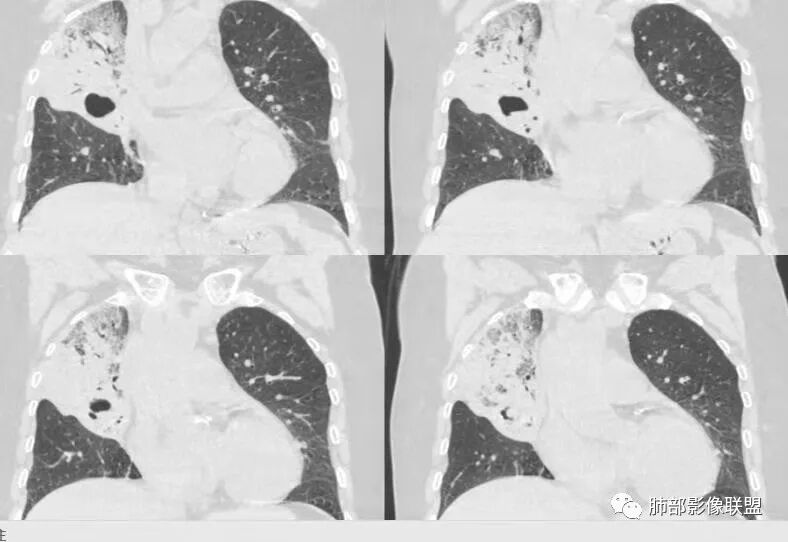

右肺上叶大片状阴影,内见僵硬的支气管,部分支气管轻度扩张,内见一空洞和液平,病灶边缘可见磨玻璃影,首先考虑恶性病变,粘液性腺癌伴感染可能。

老年女性,右肺上叶大片实变及磨玻璃密度影,磨玻璃边缘清晰,内可见小叶间隔增厚,内可见空洞,似可见分隔,叶间裂局部膨隆,纵膈窗,没有增强,枯树枝不明显,肺炎型肺癌可能,鉴别大叶性肺炎,结核?

胸CT:右肺上叶实变内可见支气管充气征,近端支气管狭窄,远端扩张,周围可见毛玻璃影,右肺中叶支气管闭塞,并可见气道壁钙化,右肺中叶体积缩小,实变内可见空洞,并可见气液平面,空洞周围可见毛玻璃样影,右肺下叶支气管开口狭窄,右肺门淋巴结肿大。纵隔窗可见病灶与壁层胸膜间隙增宽,考虑良性病变-----感染性病变------TB?

老年女性,慢性病程,咳嗽伴白色粘液痰,无发热腹痛,糖尿病,白细胞及C反应蛋白不高,血沉快,铁蛋白高。胸部CT,右肺上叶大片状实变伴磨玻璃密度影,边界不清,边缘局部膨隆,叶裂弧形下坠,实变影宽基底与胸膜相贴;右肺下叶前基底段见类似病灶;右肺中叶不张并空洞形成,空洞内见气液平面;综合考虑右肺上叶及下叶肺炎型肺癌,右肺中叶结核。

老年女性,病史1月,右肺上中叶大片状影,跨叶,上叶为主,磨玻璃为主,边界模糊,部分实变,内见空洞影和液气平面,壁光滑,支气管开口狭窄,局部有扩张,右肺门淋巴结钙化,首先考虑感染性病变,结核可能,鉴别粘液腺癌。

老年女性,咳白色粘液痰,右肺跨叶大片高密度影,密度不均匀,其内见支气管枯树征,有空洞,边缘部分清楚,叶间裂有下坠膨隆感。考虑粘液腺癌,鉴别干酪性肺炎